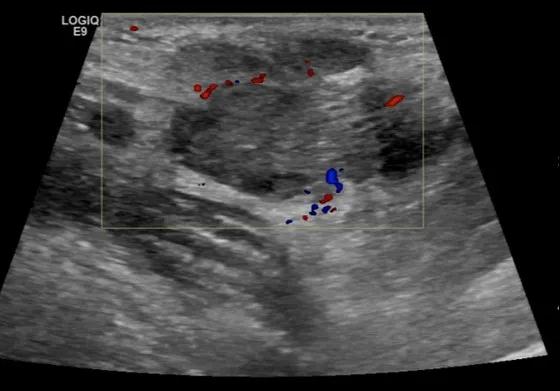

随后,徐栋教授进一步分享了五个临床实战病例,带来了更直观的热消融治疗经验。第一个病例是62岁肺癌患者,术后1年余发现双侧锁骨上淋巴结复发,侵犯神经,存在静脉回流、淋巴回流障碍,肿胀、疼痛非常明显。影像显示患者淋巴结边界不清、形态不规则,存在浸润,血流强化增强。由于患者在系统治疗后进展,且主要目的缓解症状、减瘤。局麻下行热消融术,从后向前逐层消融,热消融之后超声造影即刻评估显示完全充盈缺损,完全覆盖病灶。

(病例1图例)